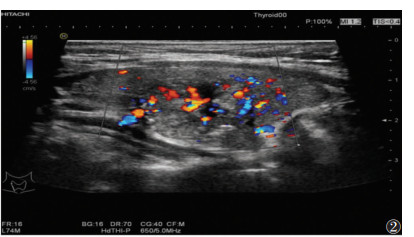

2 结果 2.1 FNAC检测结果126个结节中,102个为良性(81.0%);24个为恶性或可疑恶性(19.0%),其中,5个滤泡性甲状腺癌,7个甲状腺髓样癌和12个甲状腺乳头状癌(图 1~3)。

| 图 2 男,42岁,CDFI示右侧甲状腺肿大,形态不规则,边缘不清晰,周围可见点状血液信号 |